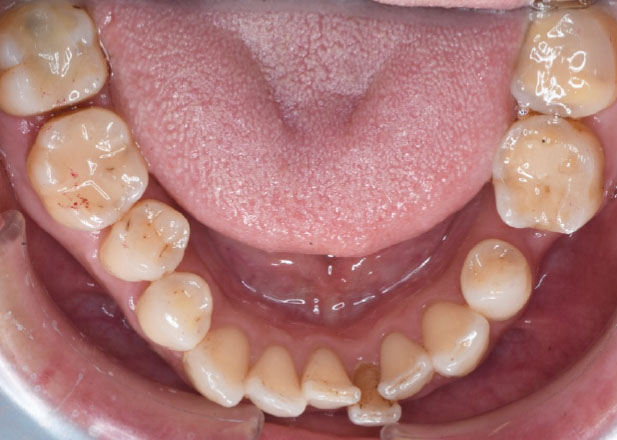

治療前

マウスピース矯正 マウスピース矯正 マウスピース矯正